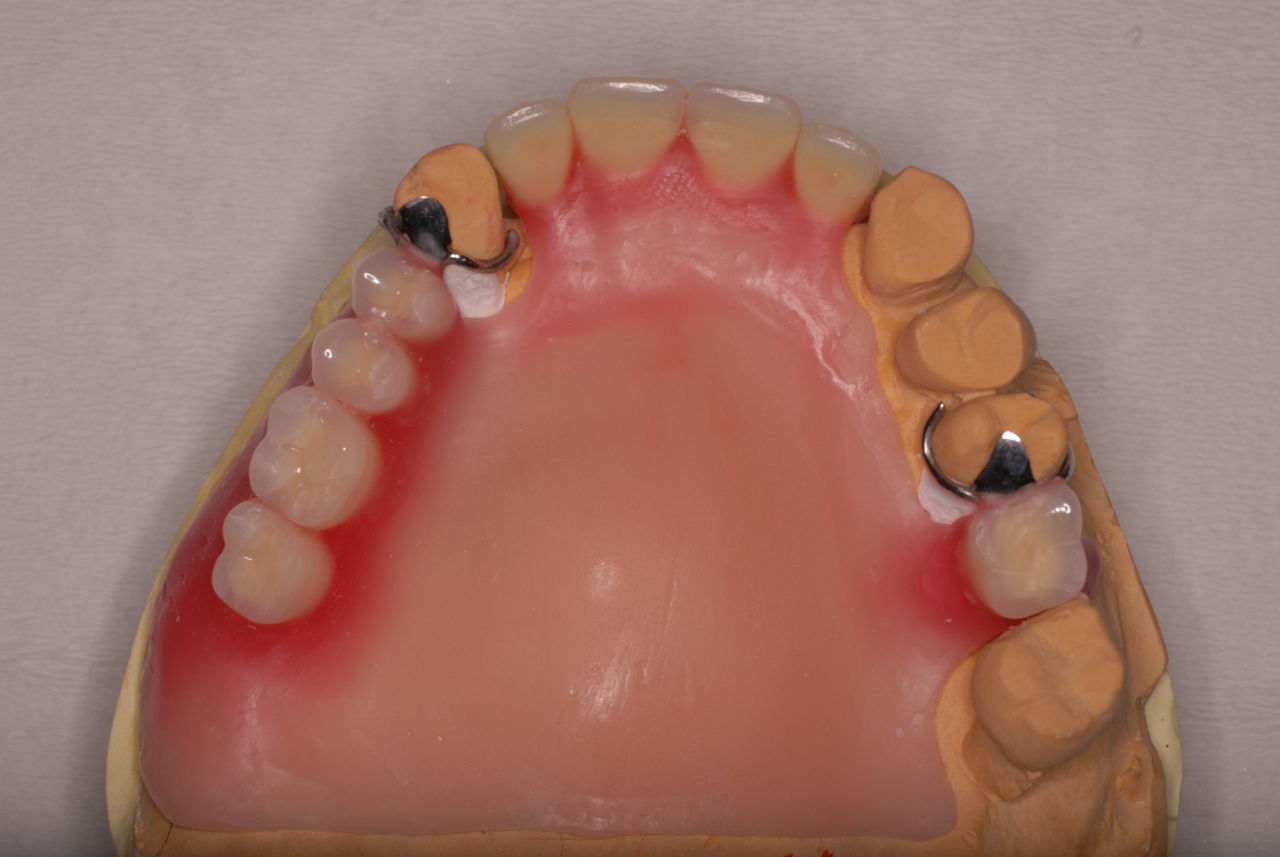

70代の患者ですが上の歯は残根一つ全て歯は無し。

下顎、殆ど歯はなく歯周病で抜けそうな歯と虫歯だらけの歯、適合の悪い銀歯が入っていてそれも虫歯と歯周病で危ない状態でした。入れ歯は下の入れ歯は入れたことがないようです。(ため息)痛くて入れたことがないそうです。

クラスプという歯を取り囲むワイヤ−が折れたりしてまともに機能していません。構造的な問題もあるのでしょうがヒビも目立ちます。殆ど使わずに御蔵入りとなったようです。値段の問題からかそうではないか判然としませんが、入れ歯というのは残りの歯や歯周病の治療がある程度完了してからでないと良い機能的な入れ歯などはできません。せいぜい治療中用の簡素な物を作成して歯や歯茎の病気が治るのを待ちながら様子をみるしかないのです。